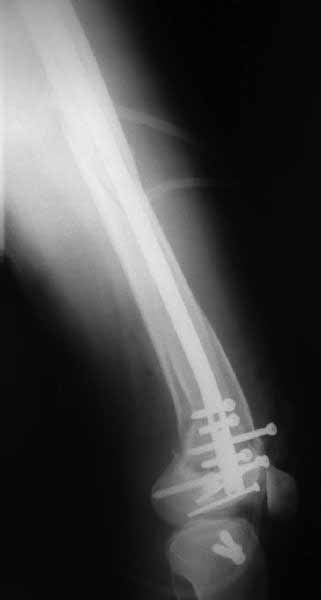

В приложении пример недавней операции, C3, открытая репозиция, фиксация мыщелков спицами и винтами, ретроградный синтез большеберцовым гвоздем 10,5 мм диаметром, винты 5 мм.

Позволю себе напомнить коллегам ещё раз, что являюсь сторонником антеградного остеосинтеза при переломах дистального эпиметафиза бедренной кости. Такая приверженность основана не на преимуществах внесуставного введения стержня или большем проценте положительных результатов. Она основана на возможности обеспечить блокирование на минимальном расстоянии от суставной поверхности в нескомпрометированной кости и, таким образом стабилизировать максимально низкие переломы. В приведенном Вами случае самый дистальный из блокирующих винтов проведен на расстоянии более 2 см от конца стержня. Из-за того, что к стержню присоединяется кондуктор, на стержне теряется 1-1,5 см его длины, где можно было разместить отверстия для блокирования. И что более важно, вместе с потерянной для этой цели длиной стержня утрачивается для размещения блокировочных винтов, пожалуй, самая ценная часть дистального эпиметафиза бедренной кости. Проблемы дистального блокирования в разных плоскостях, локализации точки ввода стержня при антеградном остеосинтезе – это всё решаемые технические проблемы. Но антеградный остеосинтез низких дистальных переломов бедра при адекватном блокировании в нескомпрометированной кости обеспечивает решение стратегической задачи – стабильный остеосинтез и возможность нагрузки.

На этом большеберцовом стержне центр ближайшего к кондуктору отверстия в 14 мм от конца. И пример был про то, что пластина тут, скорее всего, была бы не худшим выбором.